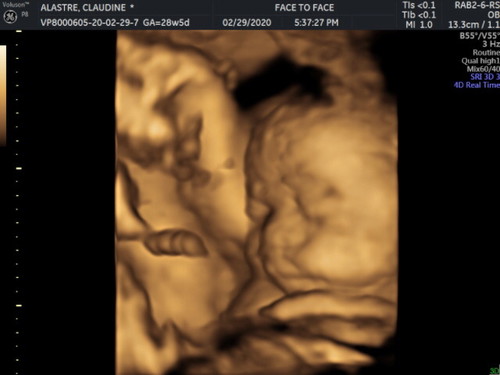

My dearest ???????, I know its not your birthday today, not even our anniversary or fathers day. But i just wanted to take a moment and tell you, I appreciate YOU. I see how hard you work for us to build and provide for our family. It must have been exhausting but you still manage to do chores. I appreciate when you get up early to make breakfast for me before I go to work because you don't want me to do things at home because of my pregnancy. And when i am having a tough day you are always there to listen to every complain and cries although i know you are probably going through something as well. But yet you still manage to encourage and give good advice to me. I know you may think these are just small things. But my point is that i see all you do and appreciate you. I am very proud of who you become and i pray that You will continue to let God mold you and direct you to the path He wants you to take?? You and our family are the best gifts i received from God ?? We love you always. ????? ???????? ?? ?? ? Love, ????? ??? ???? ? ? #?????????????????????????? ✨??